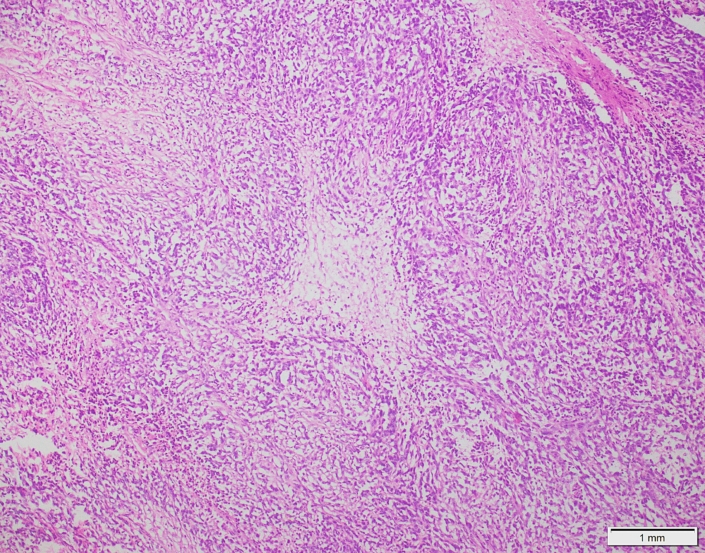

Case 03

Case presented by Dr Shaarif Bashir, FCPS (PAK), Shaukat Khanum Memorial Cancer Hospital and Reserach Centre, Pakistan